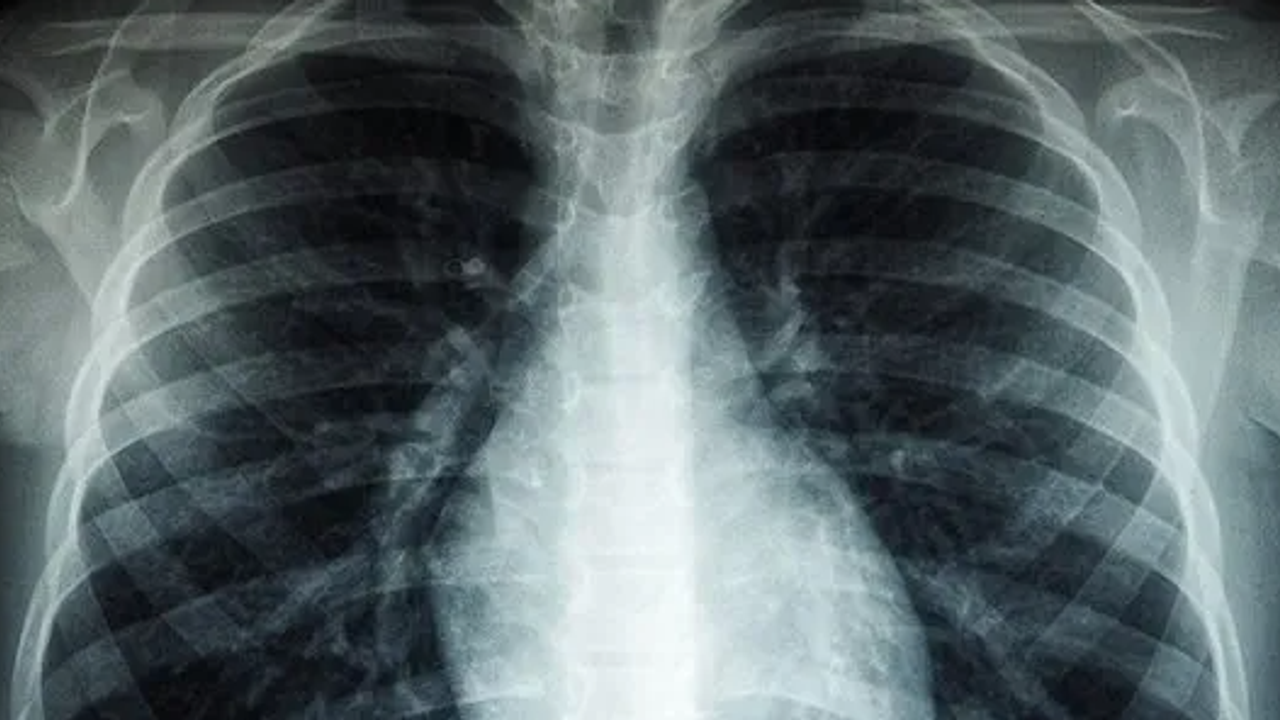

Kasım ayı, Türkiye’de akciğer kanserine dikkat çekmek ve erken tanının önemini vurgulamak amacıyla ‘Akciğer Kanseri Farkındalık Ayı’ olarak kabul ediliyor. Akciğer kanseri ise akciğer dokusundaki hücrelerin kontrolsüz çoğalmasıyla oluşan ve diğer organlara yayılabilen ciddi bir hastalık olarak biliniyor. Genellikle erken evrelerde belirti vermediği için geç fark ediliyor ve bu durumda tedavi şansını azaltıyor. En önemli risk faktörü sigara kullanımı olsa da, sigara içmeyen kişilerde de bu hastalık görülebiliyor. Pasif içicilik, hava kirliliği, genetik yatkınlık ve bazı kimyasal maddelere uzun süreli temas ileri yaşta akciğer kanseri riskini artıran diğer etkenler arasında bulunuyor. Konuya ilişkin açıklamalarda bulunan Medicana Sivas Hastanesi Göğüs Hastalıkları Uzmanı Dr. Büşra Yayla Yerlikaya, öksürük ve balgam çıkarma gibi basit görünen semptomların kanserin belirtisi olabileceğini söyleyerek, "Bu hastalık, hem dünyada hem de ülkemizde kansere bağlı ölümlerin en sık nedenidir. Ne yazık ki genellikle erken evrede belirti vermediği için geç tanı alabilmekte ve bu da tedavi şansının azalmasına sebep olabilmektedir" dedi.

Akciğer kanserinin büyük bir kısmını sigara ile ilişkili olduğunu söyleyen Büşra Yayla Yerlikaya, "Bu hastalık, hem dünyada hem de ülkemizde kansere bağlı ölümlerin en sık nedenidir. Ne yazık ki genellikle erken evrede belirti vermediği için geç tanı alabilmekte ve bu da tedavi şansının azalmasına sebep olabilmektedir. Akciğer kanserlerinin büyük kısmı, neredeyse yüzde 85-90 kadarı bilindiği üzere sigarayla ilişkilidir. Günde içilen sigara sayısı ve kullanım süresi arttıkça risk de katlanarak artar. Ancak hiç sigara içmeyenlerde de pasif içicilik de en az aktif içicilik kadar önemli bir faktördür. Elektronik sigaralar ya da ısıtılmış tütün ürünleri de sanıldığı gibi güvenli değildir. Nikotin içerdikleri için bağımlılığı sürdürürler ve ekstra pek çok kimyasal daha içerirler. Uzun vadeli zararları henüz tam olarak bilinmemektedir" dedi.

Özellikle sigara içen bireyde öksürük gibi belirtiler varsa bir uzman tarafından değerlendirilmesi gerektiğini belirten, "Akciğer kanserinin en sık belirtileri ise uzun süren öksürük, balgamda kan, nefes darlığı, kilo kaybı ve göğüs ağrısıdır. Özellikle sigara içen birinde yeni başlayan ya da karakteri değişen öksürük varsa mutlaka bir göğüs hastalıkları uzmanı tarafından değerlendirilmelidir. Erken tanı her kanser türünde olduğu gibi akciğer kanserinde de hayat kurtarır. 50 yaş üzeri ve uzun süre özellikle 20 paket yıl ve daha fazla sigara içmiş kişilerde düşük doz tomografi ile tarama yapılması, hastalığın erken evrede erken tanı sağlar ve tedavi şansını ciddi şekilde artırır. Sigarayı bırakmak her yaşta faydalıdır. Bıraktıktan sonraki on yıl içinde akciğer kanseri riski büyük oranda azalır. Çalışmalar 10 yıl sonra yüzde 50, 15 yıl sonra ise yüzde 90’a kadar akciğer kanseri riskinin azaldığını göstermiştir. Sigara içen bireylerde sabahları balgam ve öksürükler mevcut oluyor. Bu durumlarda balgamın karakter değiştirmesi ve artması önemli bir belirti olabiliyor" diye konuştu.